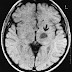

Essentiellement , une tumeur cérébrale peut être la progression anormale de cellules dans le cerveau , puis l'on considère généralement qu'il cellules cancéreuses. Vous trouverez d'autres façons la tumeur peut se propager. Le tout est que c'est vraiment motifs derrière la multiplication des cellules cancéreuses provenant d'une autre partie du corps ou peut-être les cellules de cancer sont en réalité dans le cerveau lui-même .

Donc référence aux résultats des produits chimiques dangereux en progression anormale de tumeur cérébrale. Il avait été statistiquement confirmé que 80 % des personnes de cancer du cerveau sont frappés par oligodendrogliome .

Cancer du cerveau reste probablement le plus probable probablement le cancer le plus incurable grâce à obtenir une quantité moyenne de survie de quelques années .

Un taux de survie du cancer du cerveau de cinq ans peut être influencée par un couple de facteurs y compris la taille de la tumeur , où la zone du cerveau , le cancer de l'importance en même temps que l'étape. Dans plusieurs occasions, à l'intérieur de l' état de santé général du patient peut aussi être un facteur indicatif de la survie.

Healthline.com rapporté que les enfants de 14 ans ont environ 73 pour cent de possibilité qui l'amène à être par le cancer dans le cerveau et de vivre jusqu'à cinq années plus , puisque le taux tombe à 55 pour cent avec les adolescents entre 15 et 44 . Patients d'âge moyen entre 45 et 64 possèdent un taux de 16 pour cent , et les personnes âgées possèdent un taux de survie de seulement cinq pour cent .

Le taux de survie au cancer du cerveau présenté ici s'appuie sur un résultat de membre de la famille . Le taux de survie au cancer du cerveau entier de 5 ans à l'intérieur de la période 1995-2001 a été supérieur à 33% . Les taux de survie relative à cinq ans pour le cancer du cerveau par la race et le sexe étaient les suivants:

• 32,1 % des hommes de couleur blanche

• 37,7 pour cent pour les hommes afro-américains

• 33.five pour cent des femmes de couleur blanche

• 37.five pour cent pour les femmes afro-américaines .